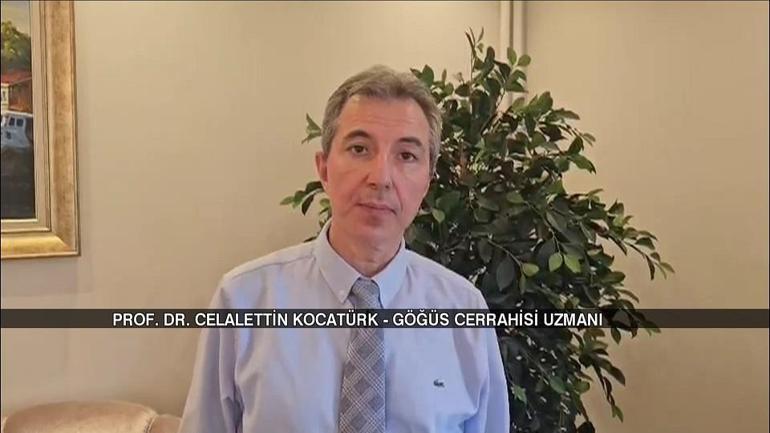

Göğüs Cerrahisi Uzmanı Prof., dünya çapında her yıl yaklaşık 2,5 milyon kişinin akciğer kanserine yakalandığını söyledi. Dr. Celalettin Kocatürk, “Maalesef 1,5 milyon insan hayatını kaybediyor. Akciğer kanseri çok sinsi bir hastalık. Erken dönemde belirti vermiyor. Tanı konulduğunda genellikle ileri evrelerde ortaya çıkıyor. Bu nedenle oldukça ölümcül.” dedi.

Kocatürk, şöyle konuştu: “Öksürük, göğüs ağrısı, halsizlik, balgamda kan gibi şikayetleriniz varsa doktora başvurmalısınız. 50 yaşındaysanız ve 20 yıldan fazla süredir sigara içiyorsanız mutlaka göğüs hastalıkları uzmanına veya göğüs cerrahına başvurmalısınız. Erken aşamada teşhis koyabilirsek, iyi bir tedavi ve ameliyatla akciğer kanserini tamamen ortadan kaldırmak mümkündür.” dedi.

En sık görülen nedenlerin tütün ve tütün ürünleri olduğunu söyleyen Kocatürk, çevresel maruziyet, hava kirliliği, kimyasal maddelere maruz kalma ve aile geçmişinin de önemli olduğunu söyledi.